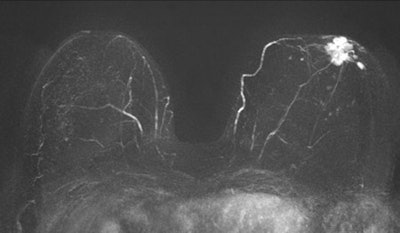

A 56-year-old woman without a family history of breast cancer had a negative screening mammogram. MRI screening revealed a large, nonpalpable breast cancer in the immediate retro-areolar region of the left breast readily picked up by the maximum intensity projection (MIP) image (below). All images courtesy of Dr. Christiane Kuhl.

These two first postcontrast subtracted (FAST) images are from the same patient.